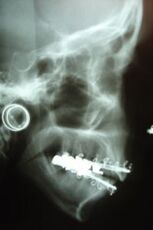

• Zahnmedizin